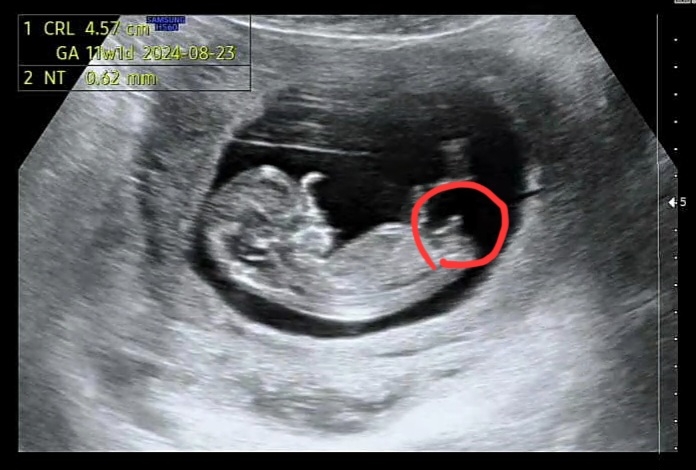

첫째는 딸이구 둘째 임신중인데 11주 2일에 초음파 보니 선생님이 "아직 확실하진 않지만 다리 사이에 뭐가 보이네요" 하고 저 부분을 콕 짚어주셨어요~ 딸딸이어도 좋지만 딸하나 아들 하나면 좋겠다 생각했었는데 아들에서 딸로 반전이 있으려나요? 주변에서 딸태몽(각종과일 복숭아 호박) 계속 꿔주셔서 딸이겠거니 했다가 초음파에 뭐가 있다니깐 기대하게 되네요😂

보이긴 왕자님같네요 !!각도법이랑 다 거의 맞긴해여 ^^; 이렇게 분명하게보이면뭐…거의:.